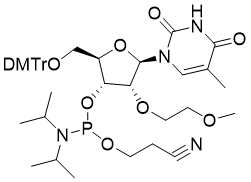

馬鞍山致研生物醫(yī)藥科技有限公司成立于馬鞍山市鄭浦港新區(qū)現(xiàn)代產(chǎn)業(yè)園。公司專(zhuān)注于生物小分子、醫(yī)藥中間體相關(guān)產(chǎn)品的研發(fā)和生產(chǎn),產(chǎn)品主要包括DNA亞磷酰胺單體、RNA亞磷酰胺單體、特殊單體以及按照客戶(hù)要求定制的RNA和DNA,并且公司提供定制合成等方面的研究服...

馬鞍山致研生物醫(yī)藥科技有限公司成立于馬鞍山市鄭浦港新區(qū)現(xiàn)代產(chǎn)業(yè)園。公司專(zhuān)注于生物小分子、醫(yī)藥中間體相關(guān)產(chǎn)品的研發(fā)和生產(chǎn),產(chǎn)品主要包括DNA亞磷酰胺單體、RNA亞磷酰胺單體、特殊單體以及按照客戶(hù)要求定制的RNA和DNA,并且公司提供定制合成等方面的研究服...